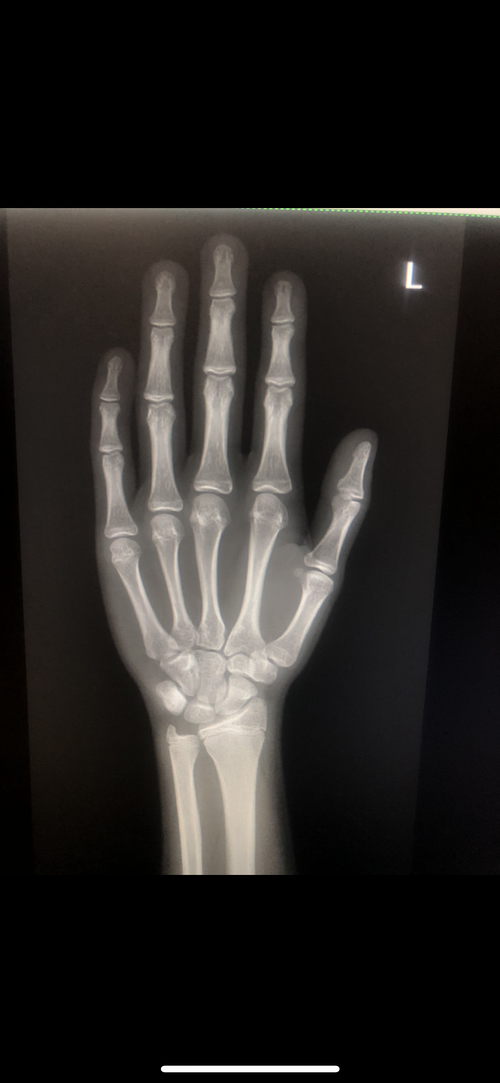

I have been diganosed ghd at a time where my g plates are almost fusing in that stage and i told my doctor abt it he said u have come too late i wouldve given u ai if u have came at 14 and said wont prescribe u now its gona ruin the gh ur ok rn nad bla bla:feelsrope::feelsrope::feelsrope::feelsrope::feelsrope::feelsrope::feelsrope: should i get ai myself or its pointless

Attachments

• IMG_2303.jpeg

IMG_2303.jpeg

I have been diganosed ghd at a time where my g plates are almost fusing in that stage and i told my doctor abt it he said u have come too late i wouldve given u ai if u have came at 14 and said wont prescribe u now its gona ruin the gh ur ok rn nad bla bla:feelsrope::feelsrope::feelsrope::feelsrope::feelsrope::feelsrope::feelsrope: should i get ai myself or its pointlessView attachment 4953277